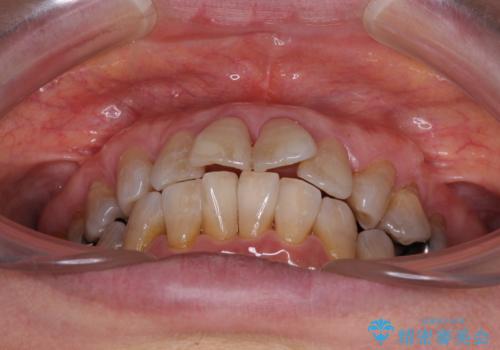

- 口元の突出感と歯の色を気にして来院された患者様です。

口元を引っ込めるために上下左右第一小臼歯4本を抜歯し、ワイヤー矯正を行うこととしました。

歯の色はホワイトニングかセラミッククラウンで対応することとしましたが、ブラックトライアングルが目立つことが予想されたため、目立つ範囲をオールセラミッククラウンで補綴することとしました。